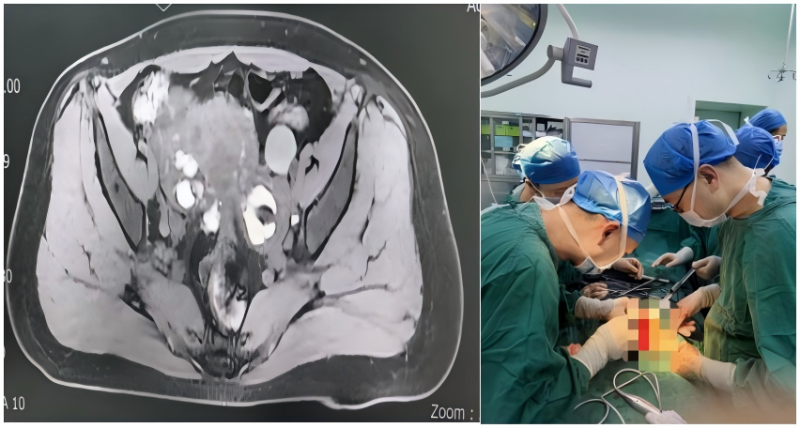

该患者为30多岁女性,长期受痛经与不孕症困扰,曾在外院经历多次盆腔手术均未取得预期效果。此次因盆腔子宫内膜异位症病灶压迫输尿管,导致一侧肾脏重度积水,肾功能面临严重损伤。由于病情复杂、手术风险高,患者此前已被多家医院婉拒。面对这一棘手情况,第十三党支部迅速响应,组织妇产科与泌尿外科党员专家组成多学科诊疗团队,以救治患者为首要任务。

依托医院多学科协作平台,在党支部及医务科的统筹指导下,妇产科、泌尿科、放射科、重症医学科、麻醉科等多科室党员和技术骨干积极参与,开展多次术前联合讨论。术前CT显示患者子宫增大、双侧卵巢囊肿、盆腹腔重度粘连,同时伴有一侧肾脏明显长大、肾盂重度扩张。手术迫在眉睫,团队围绕“彻底切除病灶、最大限度保护生育功能、精确修复输尿管、解除肾积水”的整体目标,精心准备手术方案,并制定多套应急预案,全力保障手术安全。

手术期间中,党员专家们以精湛技艺紧密配合:妇产科马超主任团队耐心细致分离盆腔粘连,完整的切除了异位病灶,为后续操作扫清障碍;泌尿外科刘强主任团队精准定位受损输尿管,实施精细修复重建。整个手术过程中,党员同志冲锋在前、严谨细致,凭借扎实的专业功底和无畏的担当精神,顺利完成了这场高难度手术。术后复查CT显示,患者肾脏形态基本恢复正常,原重度扩张的肾盂已完全回缩,经团队精心照护,患者术后一周顺利康复出院。